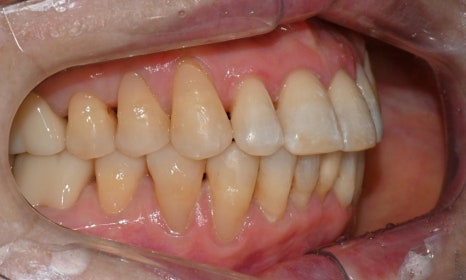

본 환자는 70세 여환으로 가만히 입을 다물고 있을 때 화난 것 처럼 보인다고 해서 튀어나온 앞니를 조금 넣고 싶다는 주소로 내원하셨습니다. 전체적인 치아 및 잇몸 상태를 검진해본 결과, 마모되어 깨진 치아도 있었고, 치경부(치아와 잇몸 사이 경계 부위)가 마모되어 파여 있는 부위도 많았습니다.

2025.2.3. 초진